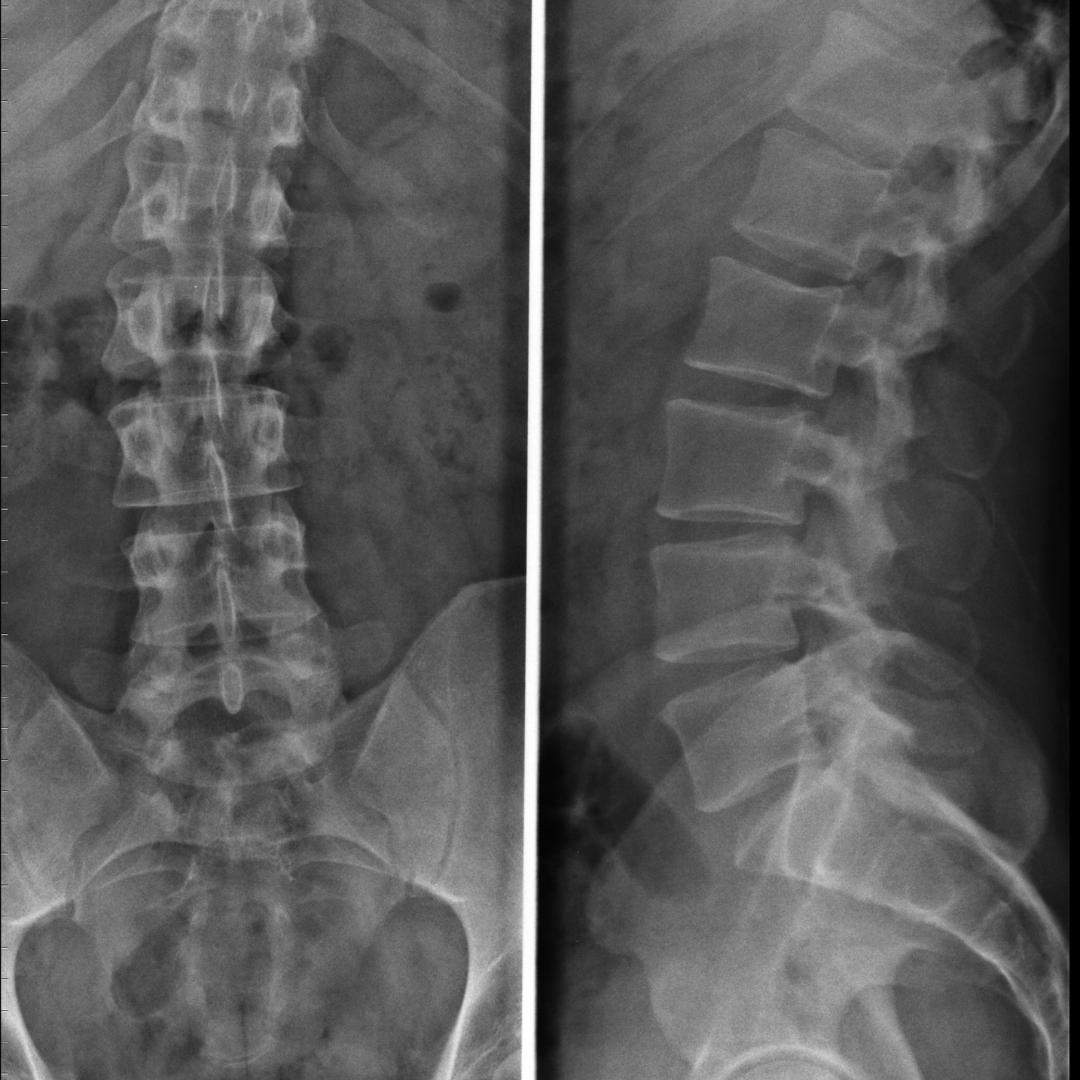

Radiografie:

• Ce poți evalua: aliniament, scolioză, cifoze/lordoze, spondilolistezis

• Când este utilă radiografia dinamică (flexie–extensie)

CT:

• Evaluarea structurilor osoase

• Fracturi, artroză, modificări degenerative osoase

• Când este preferat CT-ul

Ce vezi pe radiografie, CT și RMN

• Colaps vertebral

• Implicarea peretelui posterior

• Edem osos acut

• Leziuni ligamentare